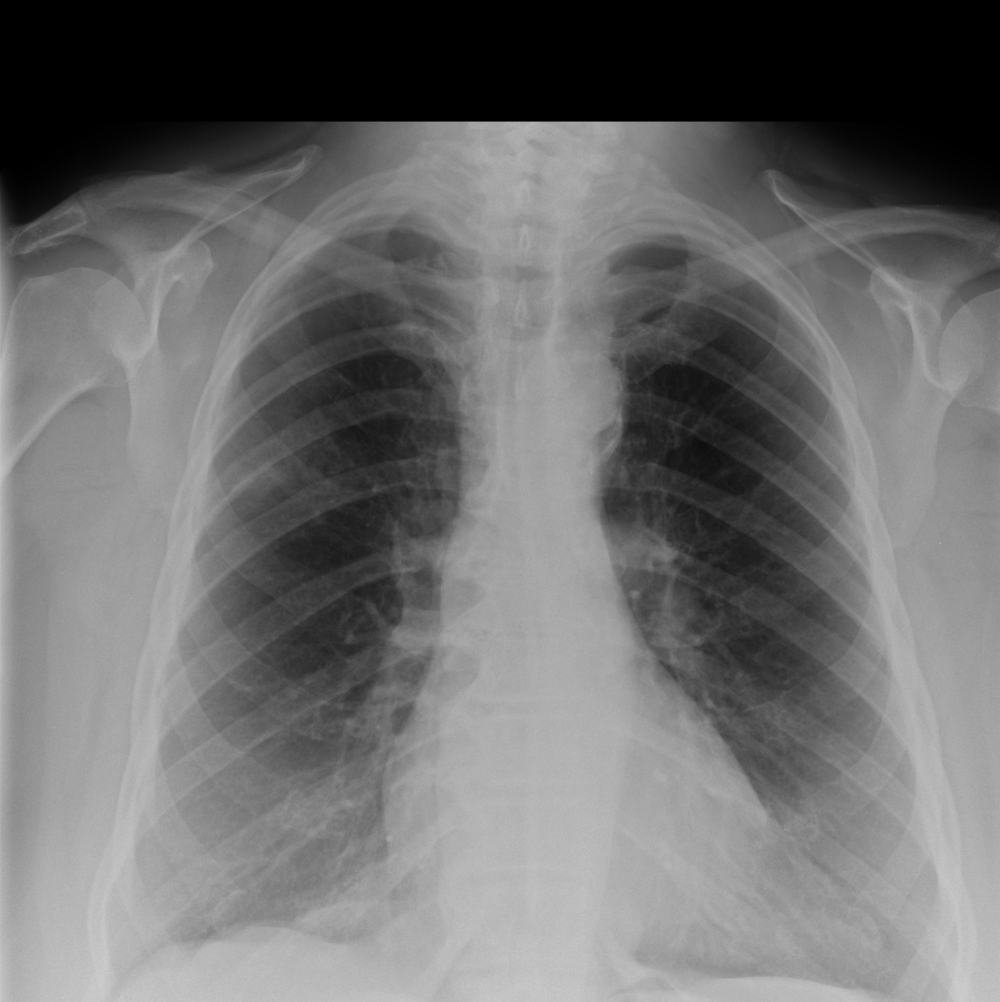

Indication

A 54-year-old male with respiratory difficulty.

Results

ChestView detected an infectious region in the right lower lobe and incidentally identified left hilar lymphadenopathy